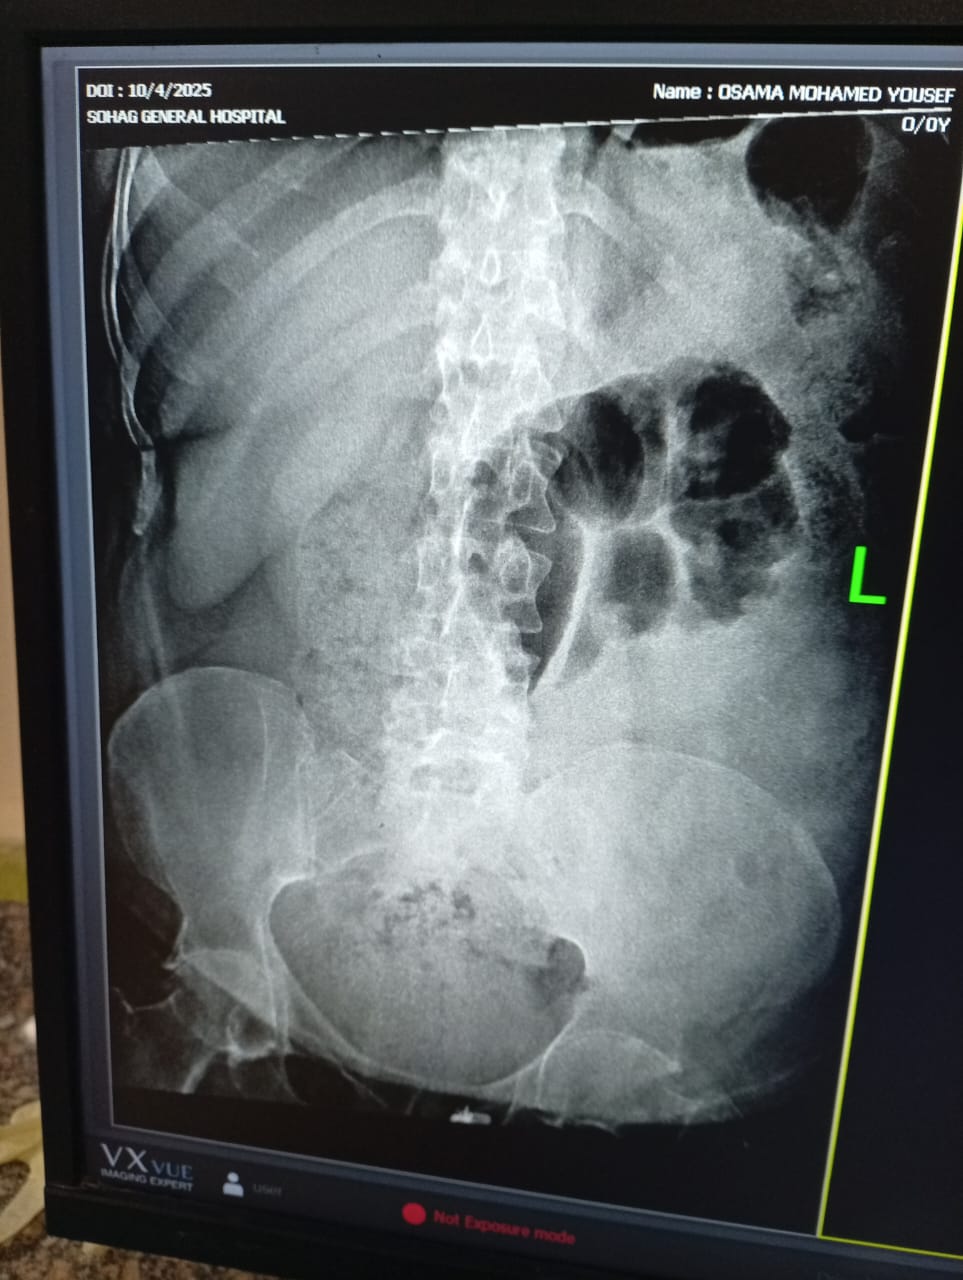

وقال عبدالله، أحد أهالى المتوفين لـ"تليجراف مصر"، إن المحامي أسامة مصاب في المستشفى بنزيف في المخ وكسور في الرقبة والساق، ونزيف دم في الفم، وهو الآن يتلقى العلاج في مستشفى الكوامل بمحافظة سوهاج، وفور إنهاء فحصة سيدخل العناية.